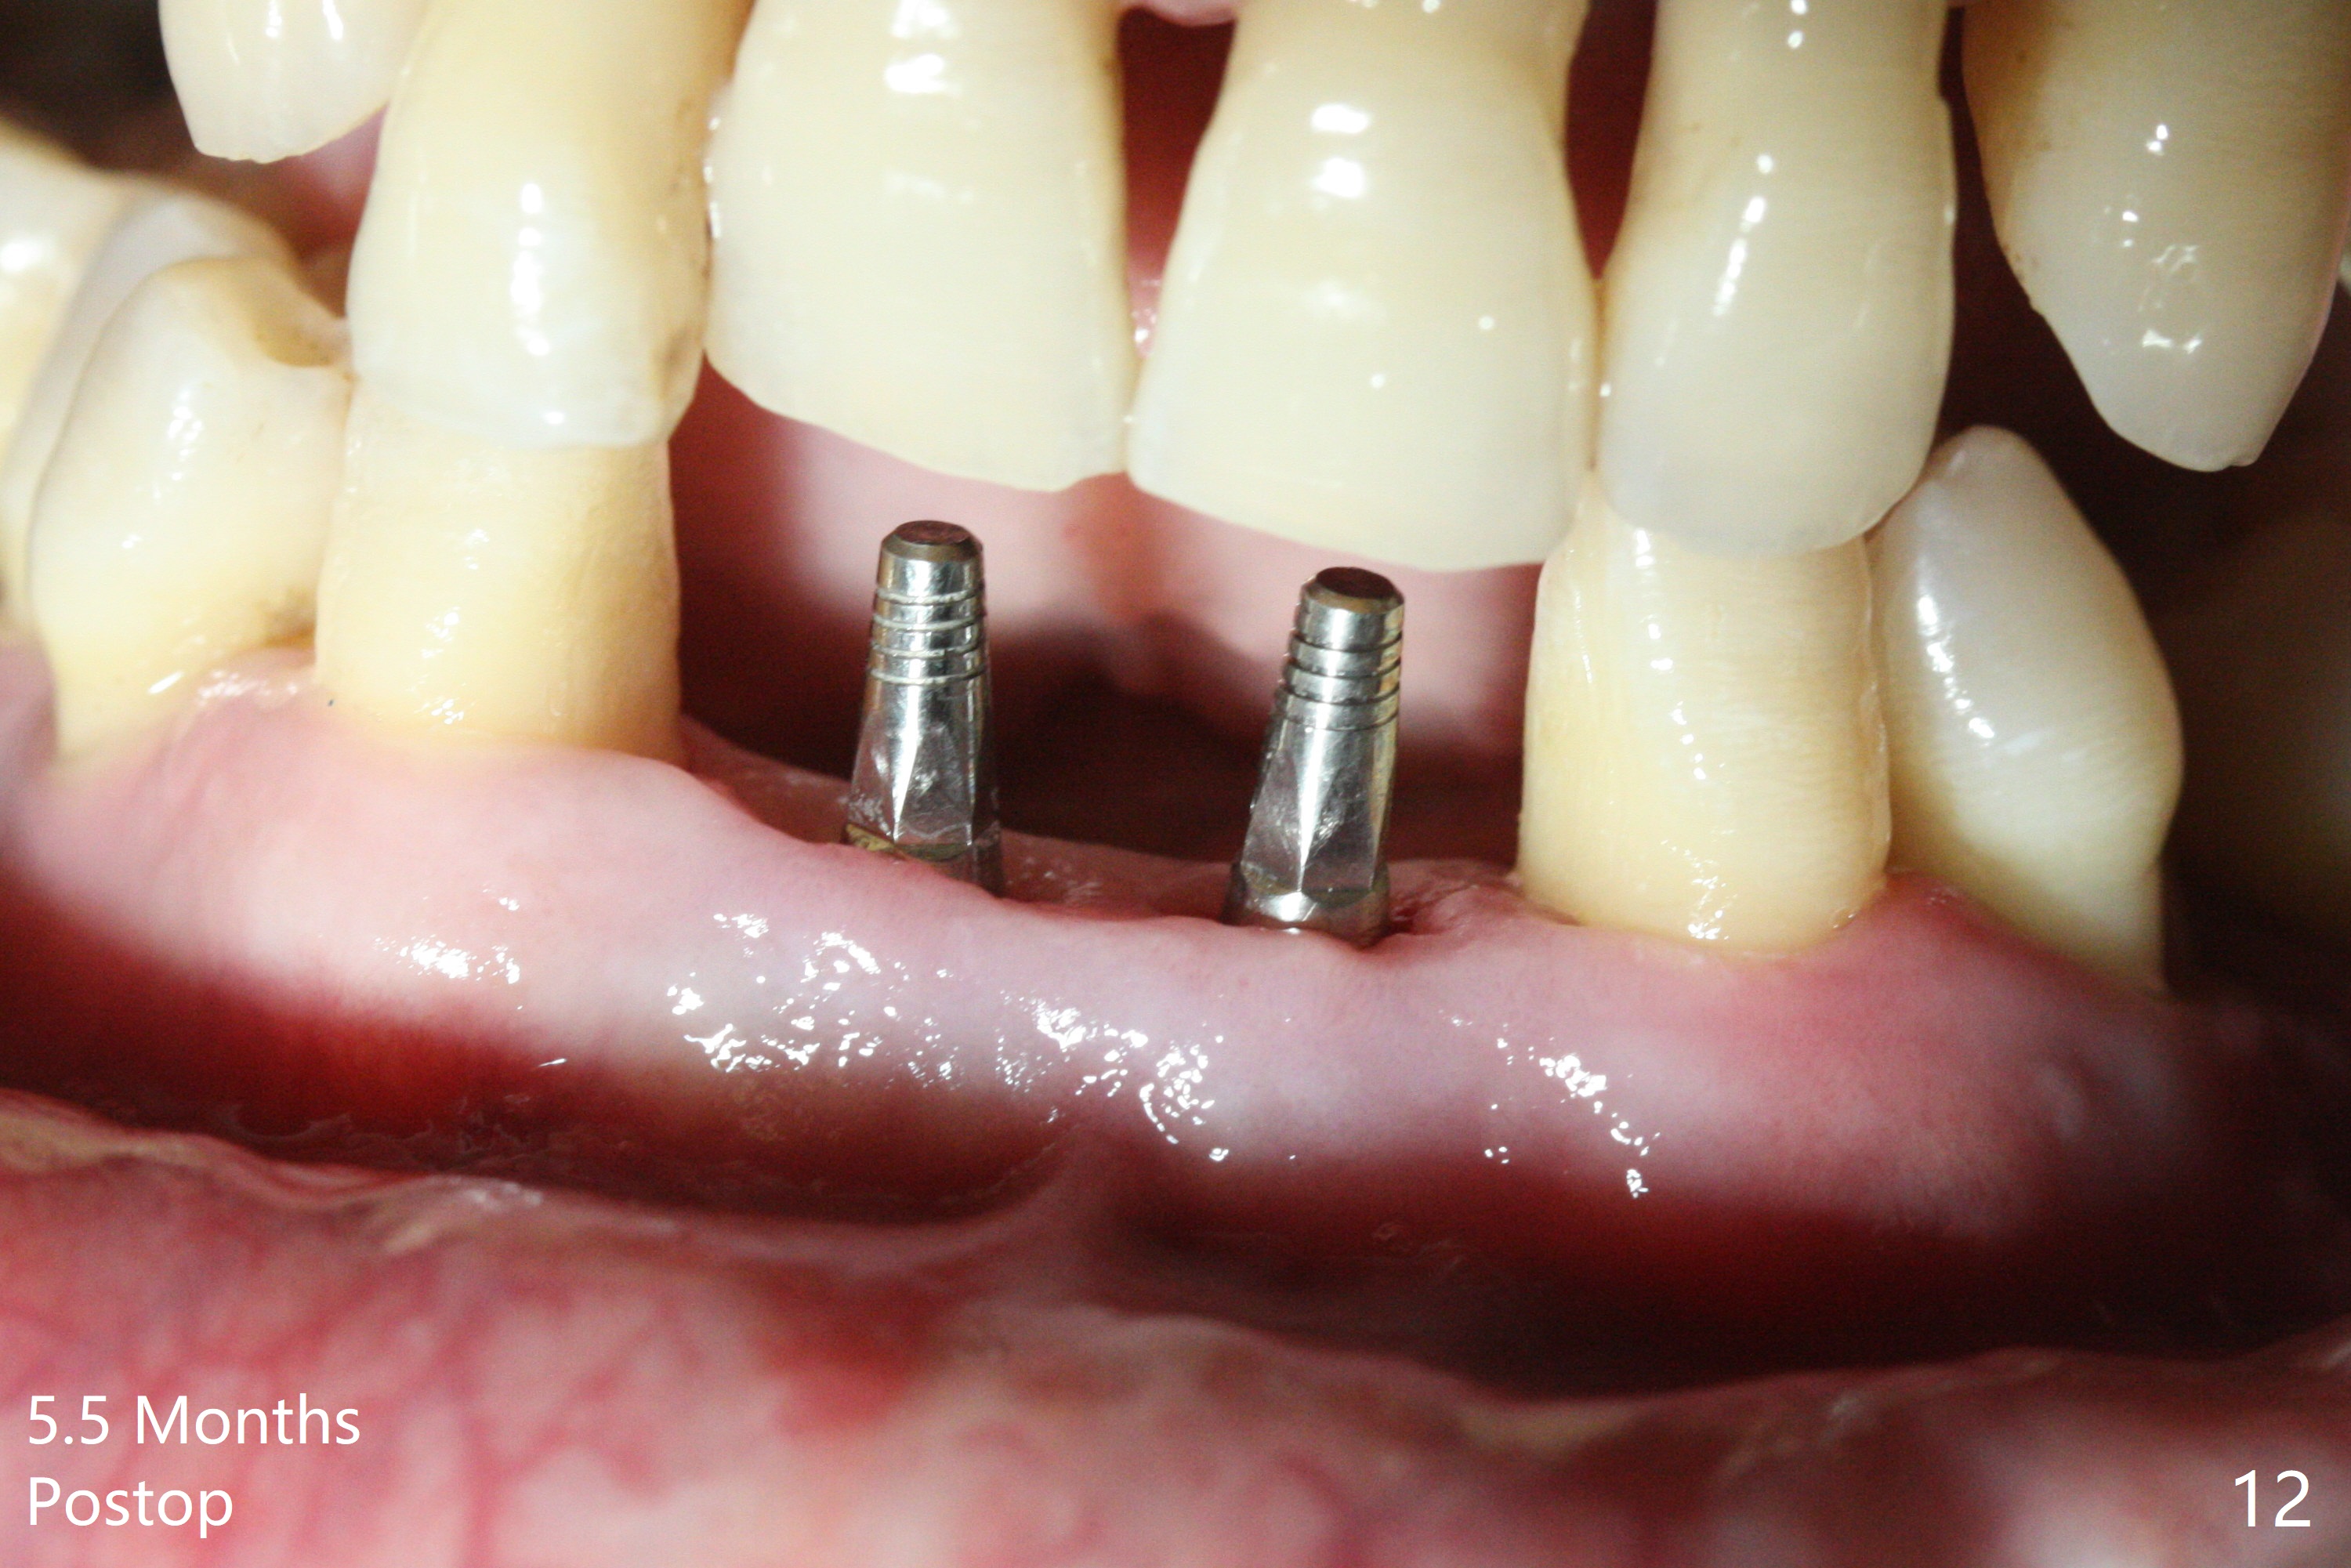

After extraction of 4 of the lower incisors, there are basically 2 sockets (#23/24 and 25/26), separated by the apparently midline bone (Fig.1 red line).  In spite of using Lindamann bur to move the 25/26 osteotomy mesially, a 3x14(2) mm dummy implant remains close to the tooth #27 (Fig.2).  The terminal branch of the Incisive Canal (<) is located between the lateral and central incisors.  A de novo osteotomy (Fig.3 (1.5 mm drill)) is made mesial to the original one (O).  While the 3x14(2) mm dummy implant is incompletely placed at #25/26, a 3x14(4) mm 1-piece one is placed at #23/24 (Fig.4).  Finally the same implant is placed at #25/26 with placement of mineralized cortical/cancellous bone (Fig.5 *).  When the large sockets are sutured, the supraerupted teeth #7-9 touch the lower gingiva (Fig.6).  The incisal edge is reduced for clearance (Fig.7).  Periodontal dressing is less likely to be dislodged with the incisal edge reduction (Fig.8,9).  A provisional FPD is fabricated 1 week postop.  Hard (Fig.10) and soft (Fig.11,12) tissues heal 5.5 months postop.  The patient returns for crown cementation 3 months post impression (9 months postop, Fig.13,14).